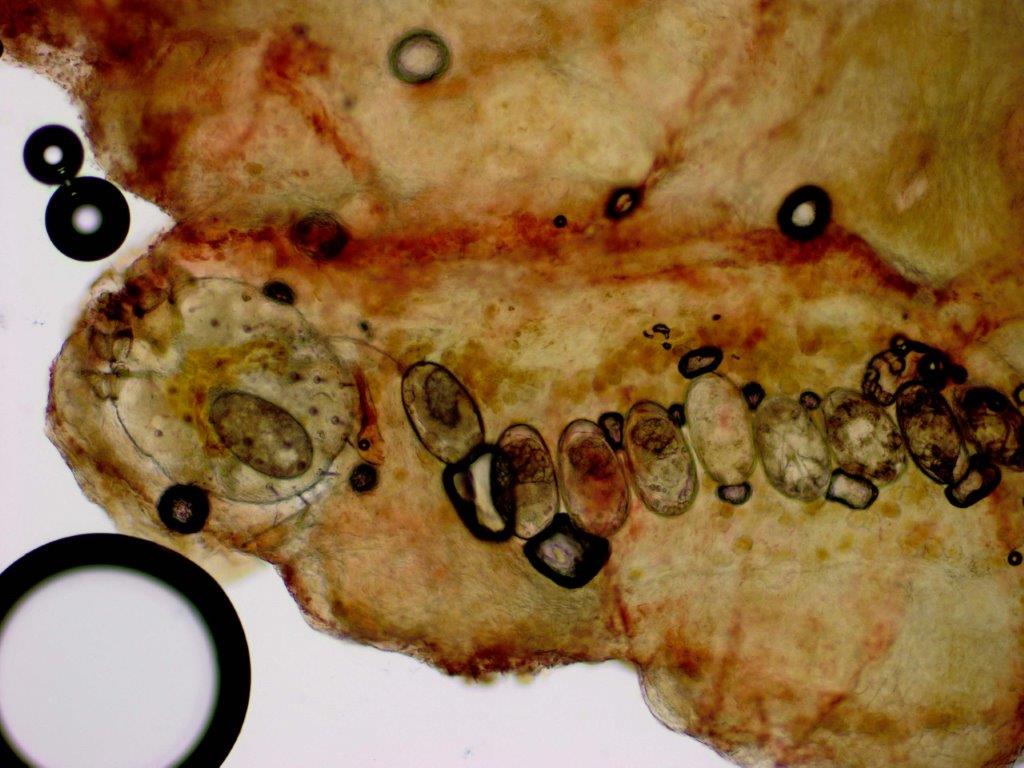

De huidschilfers zitten vol mijten en jongere mijtenstadia. Het volstaat om wat schilfers af te schrapen van een hyperkeratotisch schilferend gebied en daar een KOH-preparaat van te maken, daar moeten dan tientallen mijten en eieren in te zien zijn om de diagnose scabies crustosa te mogen stellen. Deze schilfers zijn zeer besmettelijk. Door het krabben kunnen de met schurftmijt beladen huidschilfers door de kamer dwarrelen en anderen besmetten (verzorgers, medepatiënten, bezoekers, huishoudelijk personeel). Als een patiënt met scabies Norvegica in een instelling verblijft is dat een risico voor het personeel en gelden strengere isolatiemaatregelen. Iedereen die in de kamer geweest is moet preventief worden behandeld met éénmalig ivermectine. Zie ook de richtlijn van het RIVM voor de aanpak van een uitbraak van scabies. In instellingen indien mogelijk de patiënt om de week verplaatsen naar een schone kamer en de oude kamer 1 week niet betreden.

Scabies mijten in het KOH preparaat

Mijten bij scabies crustosa Mijten bij scabies crustosa